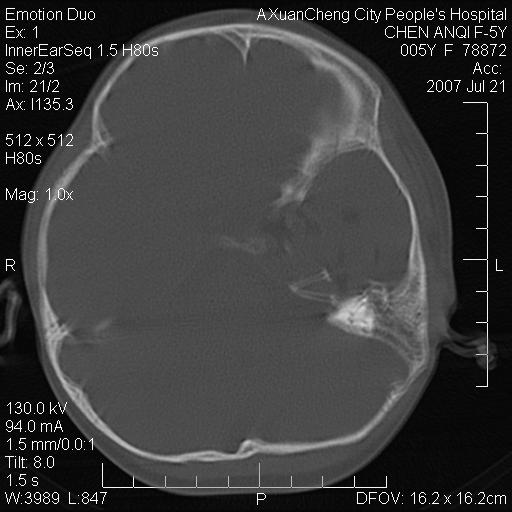

标题: PED0273:5岁,左耳流脓痛疼一周,颅底骨质破坏 [打印本页]

标题: PED0273:5岁,左耳流脓痛疼一周,颅底骨质破坏

患儿5岁,左耳流脓痛疼一周,左外耳道肉芽组织填塞 软组织窗显示病灶内结节状低密度影为气体密度

左侧中耳炎并胆脂瘤,左颞骨岩部骨质破坏并颅内感染积气。

考虑化脓性中耳乳突炎伴胆脂肪瘤形成并左颞叶感染,不除外合并嗜酸性肉芽肿.